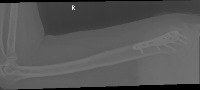

trish abnormal/normal Computer Vision Project

Medical Diagnostics: The model can be used in hospitals, clinics, or doctor practices to help provide a quick preliminary diagnosis for patients, especially in urgent care settings. Identifying fractures and hairline fractures can expedite treatment and intervention plans.

Telemedicine App: The model can be integrated into telemedicine applications to provide virtual first-line diagnostics for patients who cannot readily access medical facilities. This is particularly useful in remote areas and for elderly or disabled people.

Emergency Rescue: The model can be used by rescue teams in disaster-stricken areas to quickly identify serious injuries that need immediate attention, allowing for more informed decision-making and prioritization of patients.

Training Medical Students: This model can be used to educate medical students in the process of identifying fractures and hairline fractures, providing valuable, hands-on training experience without the risks associated with real-world diagnostics.